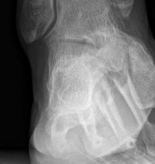

the level of the syndesmosis (Fig 2.3-1). A computed tomographic (CT) scan showed a fracture of the posterior tibial plafond with the fracture line extending from midline of the medial malleolus into the incisura fibularis, with impaction and incarceration of joint fragments (Fig 2.3-2).

Fig 2.3-2a–c Computed tomographic images. - Coronal split of the medial distal tibia.

- Incarcerated impacted articular fragment.

- Fracture line extends across the entire width of the posterior distal tibial articular surface.